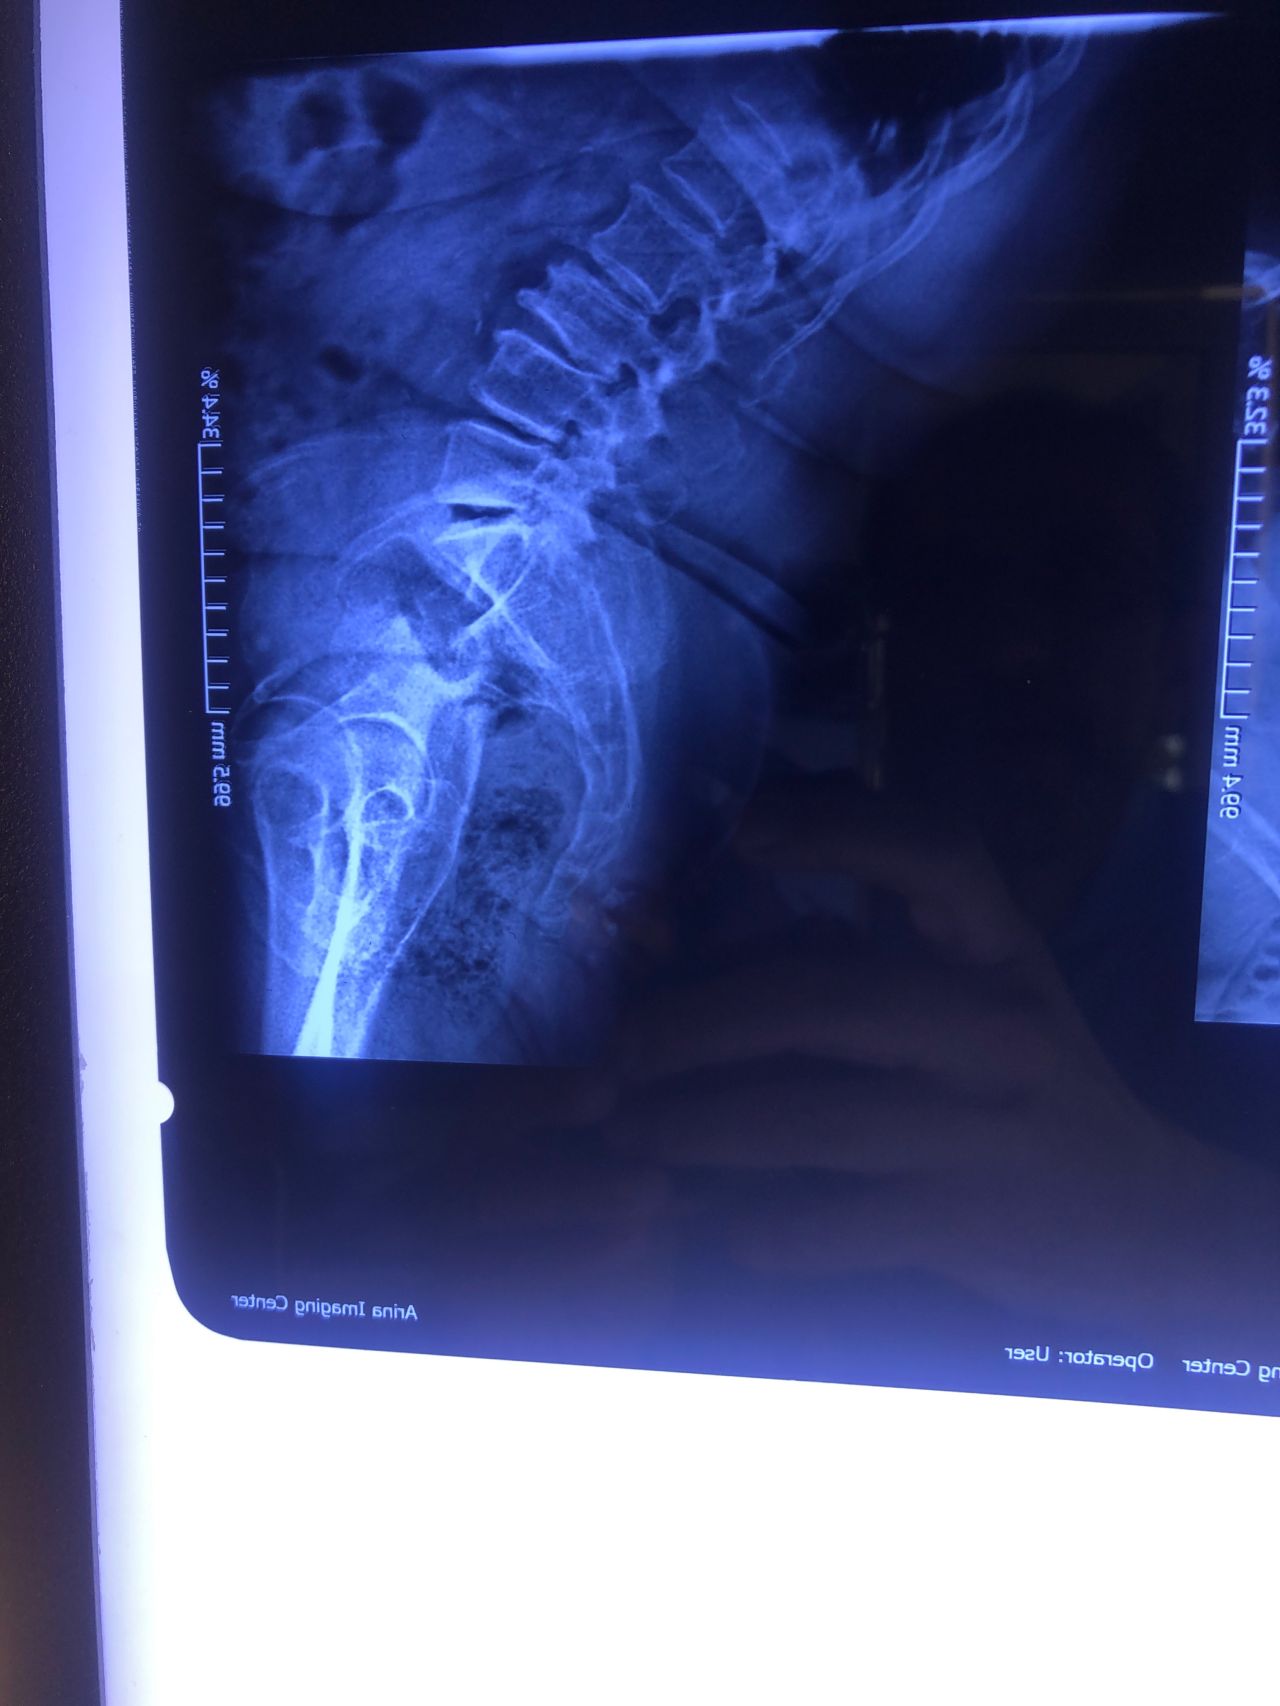

Case 19

59 yrs old female today was presented to my office few days ago with low back pain in walking. Had history of fall 4 years ago which was resulted in L 3 fracture. She had sement injection in L3.

I ordered DEXA ( had osteopenia in hip) and dynamic lumbar spine x ray Please mention what would be your plan of management. If you decide to give her treatment what kind of treatment(adjustment or decompression or other treatments)whould be suitable for her? Doctors of chiropractic can decide and come up with good plan of management and treatment for these patients and are well trained when they have to refer these patients for surgery or pain management clinics. Proper selection of these kind of patients is another important fact that can be done precisely by chiropractors.